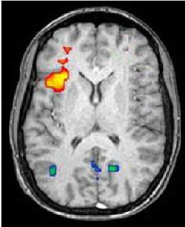

Un articolo scientifico diventa più credibile e interessante se presenta una mappa di attivazione neurale.

Tutti hanno sentito parlare, in termini di un riduzionismo ingenuo, che il tale neurotrasmettitore "causa" l'innamoramento, o la tale area cerebrale "è responsabile" della gioia piuttosto che dell'odio o del dolore. Questa volta però la conferma dei sospetti sulla tendenza riduzionistica dell'informazione scientifica viene dagli stessi studiosi della mente che con un semplice esperimento pubblicato sulla rivista Cognition (dove l'articolo è scaricabile per intero solo a pagamento) hanno verificato una stretta correlazione tra la presenza di un grafico rappresentante l'attività cerebrale (brain imaging da fRM) e il giudizio di affidabilità scientifica dato dai lettori.

brain imagingIn pratica, se c'è una di queste neuro-immagini l'articolo guadagna attenzione e credibilità anche da parte di lettori esperti (come erano gli studenti di psicologia sottoposti all'esperimento), mentre se lo stesso testo viene presentato senza questo grafico il gradimento scema. Gli autori dello studio sostengono che alla base del fenomeno vi sia una sorta di “neuro-realismo: un giudizio acritico di realtà legato al semplice fatto dell’esistenza di un’immagine intuitivamente riconoscibile del fenomeno mentale”. Se da un lato questo preoccupa i neuroscienziati perché induce una visione semplicistica del rapporto cervello-mente in cui ad un'area o ad un fenomeno chimico-fisico vengono associati specifici processi cognitivi, dall'altro sono gli stessi studiosi a confermare che il crescente interesse per le scienze cognitive nasce proprio da questa visione ingenua, in cui si possono “vedere” processi mentale prima troppo fumosi o “filosofici”.